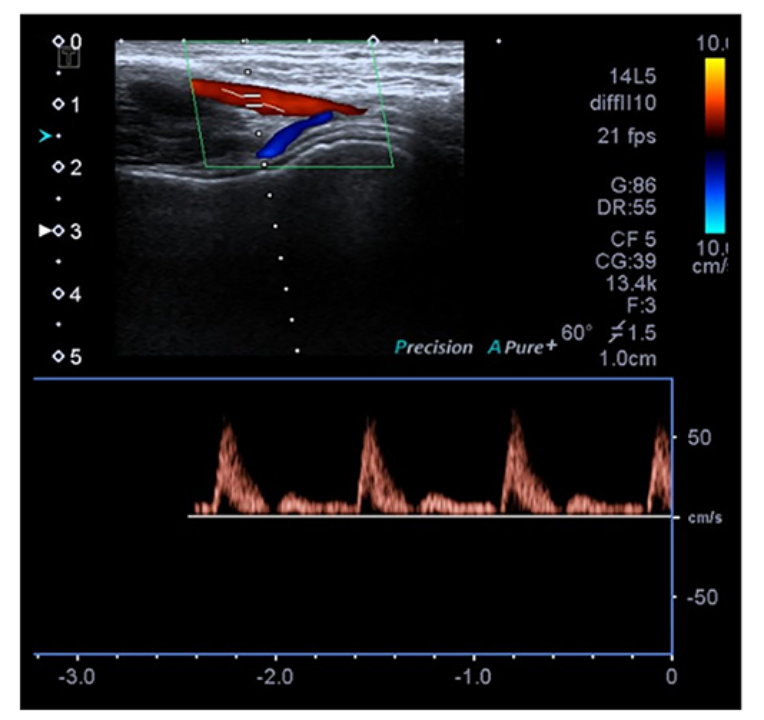

超声对早期RAO的评估

早期桡动脉闭塞(RAO)被定义为在24小时内发生的桡动脉闭塞。在移除TR-Bands后进行24小时的超声检查。如果通过多普勒超声无法检查到桡动脉血流,则视为早期桡动脉闭塞,并注意患者是否有前臂疼痛或血肿(见图3、图4)。

图3:多普勒超声无法检出桡动脉血流,考虑为早期RAO